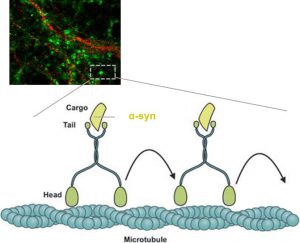

Τίτλος Ερευνητικού Έργου: Διερεύνηση των μηχανισμών μεταφοράς και έκκρισης της πρωτεΐνης α-συνουκλεΐνης με σκοπό τη διαλεύκανση των αιτιών παθογένειας στη Νόσο του Πάρκινσον.

Επιστημονική Υπεύθυνη: Εμμανουηλίδου Ευαγγελία